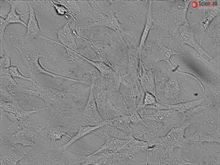

Human Cardiac Fibroblasts

Cardiac fibroblasts (CF) provide structural support for cardiac myocytes and are responsible for extracellular matrix synthesis in the heart during growth and pathophysiological conditions. CF are an important cellular component of myocardial responses to injury and the source of paracrine growth factors. CF proliferation and synthesis of matrix is essential for scar formation at sites of myocardial infarction and cardiac fibrosis. CF cultures have been widely used as a model to study the cardiac matrix remodeling by physiological (exercise) and pathological (hypertension) stressors. (SC6300)